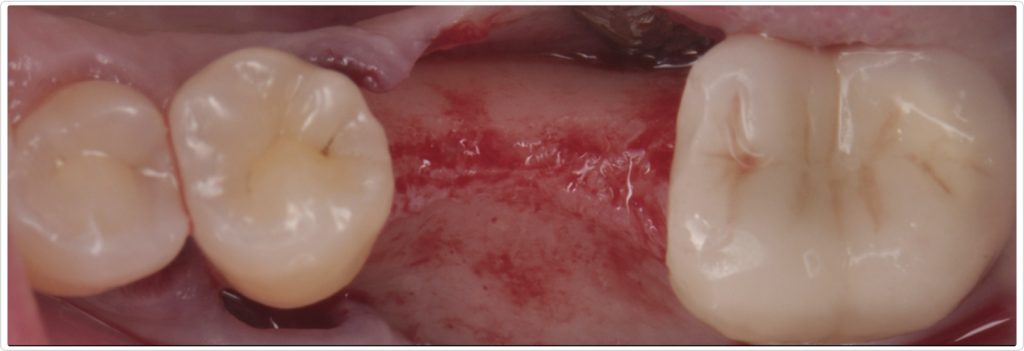

Flap design and elevation

The surgical intervention began with a crestal incision at the edentulous site, extending to sulcular incisions on teeth #18, #20, and #21 (Fig. 3). A full-thickness flap was elevated beyond the mucogingival line to expose the bone while preserving flap thickness. This approach ensured adequate visibility and access for the bone grafting and implant placement procedures.